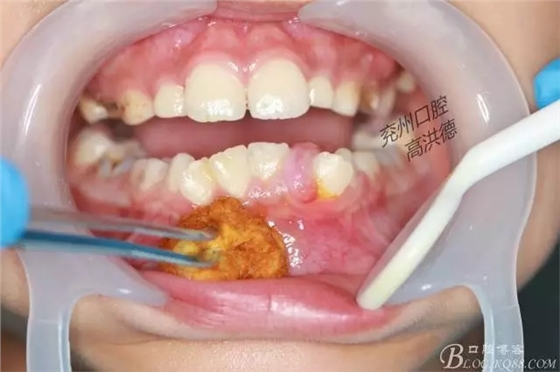

開始切除

繼續(xù)切除

切除物

此病例以手術(shù)為主,傳統(tǒng)術(shù)式拔除患區(qū)牙齒去除部分牙槽骨防止復(fù)發(fā),往往病人不能接受,而容易復(fù)發(fā)。保留牙齒,使用激光手術(shù)切除腫物,可對牙周膜和牙槽骨有一定燒灼作用,減輕了患者術(shù)后復(fù)發(fā)的幾率。術(shù)中出血少,安全無痛,術(shù)后不影響進食,臨床中值得大力推廣使用。